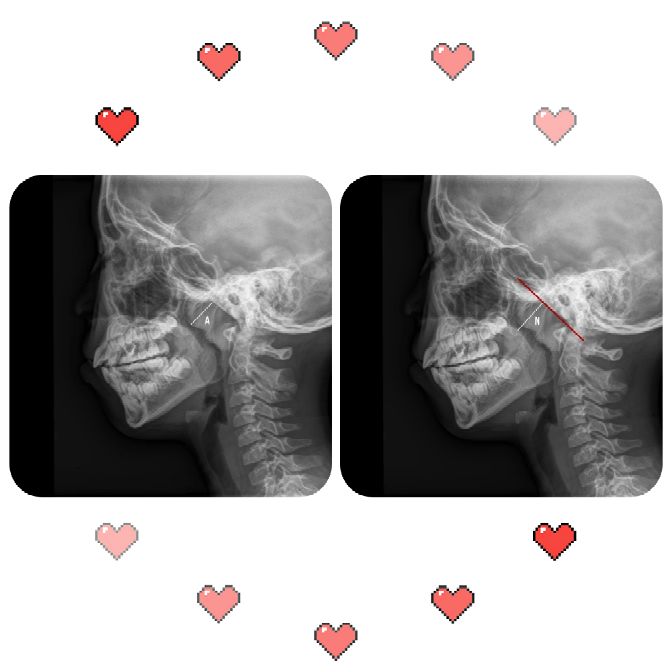

现在国内外有关腺样体肥大的标准和手术指征,首选鼻咽部侧位X线平片。

(1)腺样体(Adenoid,A)厚度

(2)鼻咽腔(Nasopharyngeal,N)宽度

用腺样体-鼻咽腔比率A/N值来评估腺样体大小与鼻咽腔阻塞情况。

腺样体厚度(A)的测量:腺样体最突点至枕骨斜坡颅骨外侧面的垂直距离为腺样体厚度。意义:>13mm,就会出现鼻咽腔气道变窄,甚至闭塞。

鼻咽腔(N)的测量:腺样体最凸部鼻咽腔的宽度,即垂线的反向延长线与硬腭后端或软腭前中部上缘的交点和枕骨斜坡颅外面切线的垂直距离。